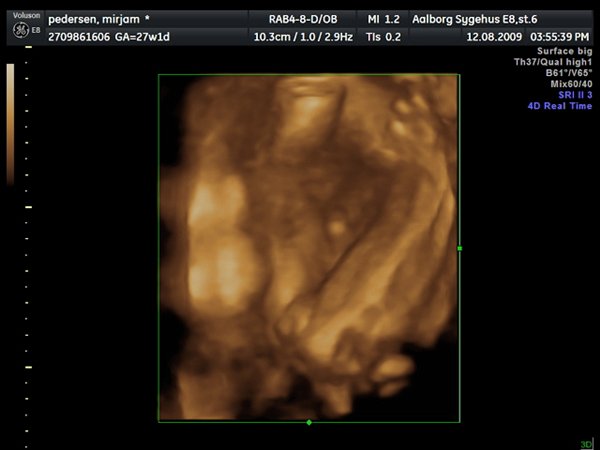

Så var jeg til 3D scanning, og det er en lille PRINSESSE

Hun var bestemt ikke samarbejds villig, vi skulle ihvertfald ikke bestemme hvordan hun sku ligge, så hun lå med hænderne oppe foran hovedet og somme tider med benene oppe foran os.. Så jeg fik rabat kom af med 800kr og han scannede mig ca 50 min. Han sagde hun vejede 990 gram

ups fik ikke billeder tilføjet

Vedhæftede fotos (klik for at se i fuld størrelse)